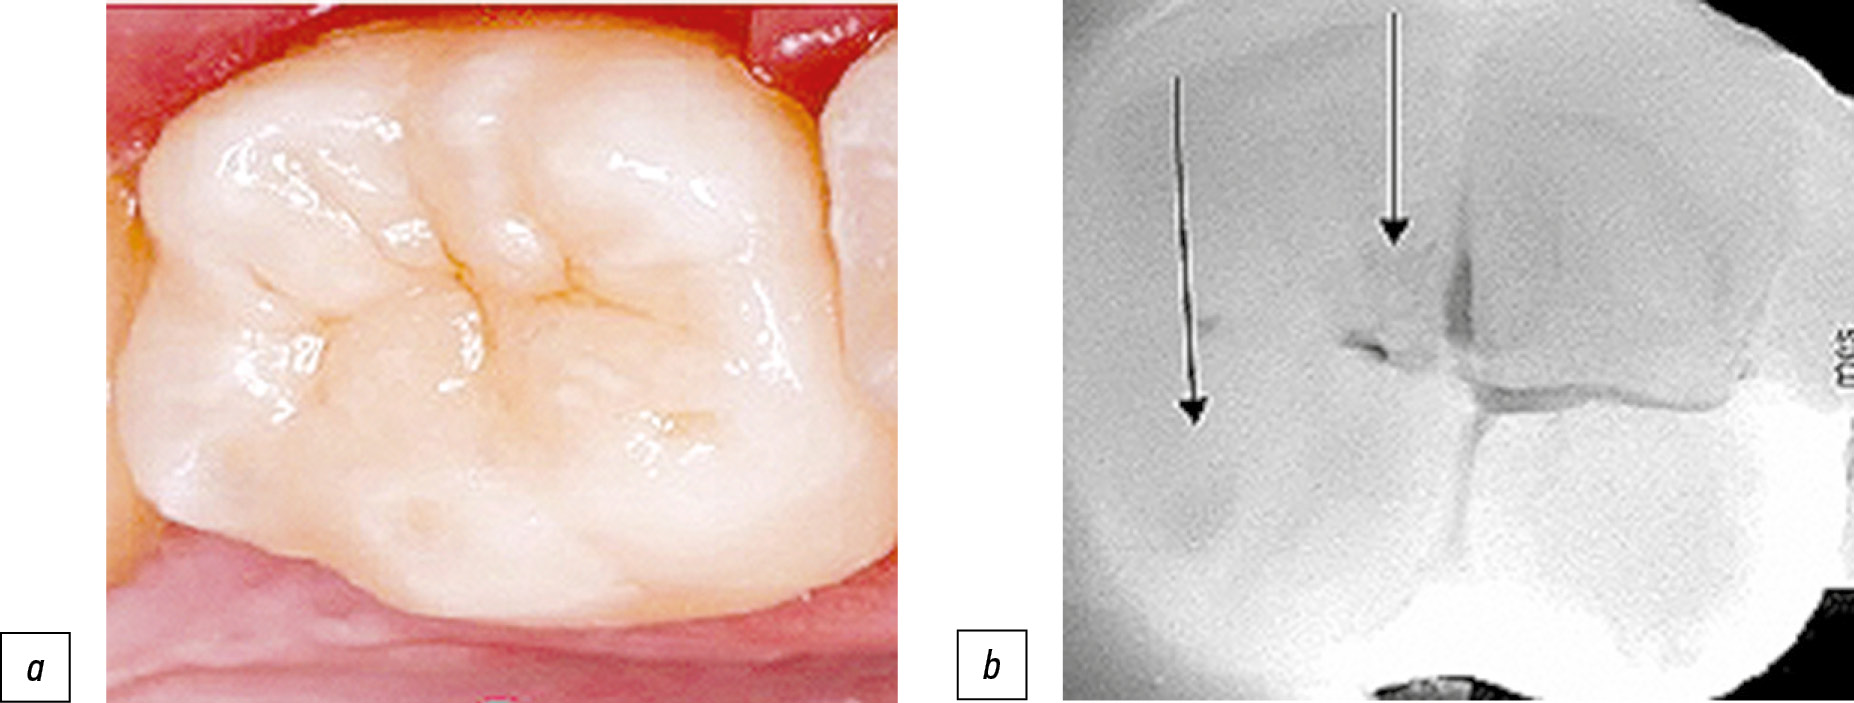

Во второй группе обследованных обнаружили гомозиготный полиморфизм С/C гена СА12 (rs 72748935) у 32 человек (57%). Индекс ИГР-У — 1,16±0,22, что интерпретировали как удовлетворительный уровень гигиены. Показатель КПУ, определённый стандартным методом, составил 13,13±1,22. Однако при использовании трансиллюминационного метода мы отметили увеличение показателя в 1,3 раза — до 16,93±1,43 (p=0,04). В ходе исследования обнаружены несколько очагов деминерализации твёрдых тканей зубов с дистальной и медиальной контактной поверхности моляров и премоляров, которые не были выявлены при обычном осмотре. Диагностировано также нарушение краевого прилегания ранее установленных реставраций (пломб) (рис. 5). Уровень рН в смешанной слюне составил 6,4±0,1 и указывал на сдвиг данного показателя в сторону кислых значений, что, вероятно, способствовало возникновению начальных стадий кариеса эмали (рис. 6). Лабораторный анализ 25(ОН)D в сыворотке крови во второй группе показал, что концентрация витамина D соответствовала значениям нормы — 28,7±0,7 нг/мл.

Рис. 5. Пациент В., 23 года, осмотр зуба 4.7: a — инструментальный способ, кариозная полость не определяется; b — трансиллюминационный метод, кариозная полость визуализируется в виде очага обширного затемнения на жевательной и дистальной контактной поверхности (показано стрелками).

При поддержании должной гигиены полости рта ИГР-У составил 1,13±0,15. При инструментальном осмотре выявили значение индекса КПУ 15,10±1,12 (за счёт удалённых и кариозных зубов). Применение метода лазерной трансиллюминации повысило данный показатель до 17,92±1,37 (p=0,04), что указывало на высокую интенсивность поражения твёрдых тканей зуба кариесом. Кроме того, обнаружено наличие скрытых повреждений не только на контактных поверхностях моляров и премоляров, но и в области пигментированных фиссур жевательных поверхностей. Несмотря на то, что визуально патологический очаг выглядел поверхностным, объём деминерализованной области затрагивал средние и глубокие слои дентина. Дополнительно установлены повреждения эмали в области ранее выполненных композитных реставраций (рис. 7).

Рис. 7. Пациент Р., 24 года, осмотр зуба 3.5: a — инструментальный способ, кариозная полость не определяется; b — трансиллюминационный метод, кариозная полость визуализируется в виде очага обширного затемнения с контактной медиальной поверхности (показано стрелкой).